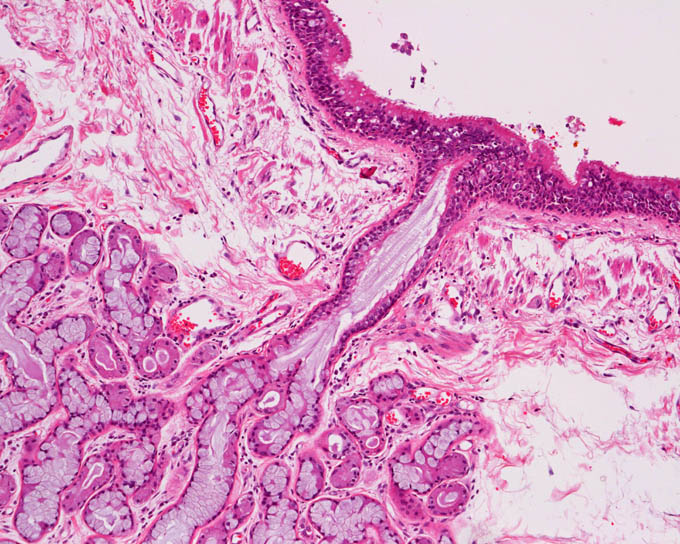

気管と気管支粘膜は多くの杯細胞を含む偽多 列線毛上皮で覆われ、固有層には混合腺である 気管腺あるいは気管支腺が存在する。 気管支は分岐を繰り返して小葉に至り、細気 管支となる。細気管支では気管支軟骨や分泌腺 が存在しない。気管の粘膜上皮は、線毛細胞と杯細胞からなる多裂円柱上皮である。 線毛細胞 については勉強したので今回は杯細胞。 杯細胞は小腸、大腸、気管支、結膜などの 上皮に散在気管支肺胞系の上皮組織の正常構造は図1に 示す通り であるそ の構造には部位によりかなり差異がみられ る 図1 気管支肺胞系の上皮細胞 気管から気管支にかけては,円 柱線毛上皮で覆われて いるこ の部位には,線 毛細胞(ciliated cell),杯細胞

病理標本 気管支 正常 新潟大学医学部臨床病理学分野